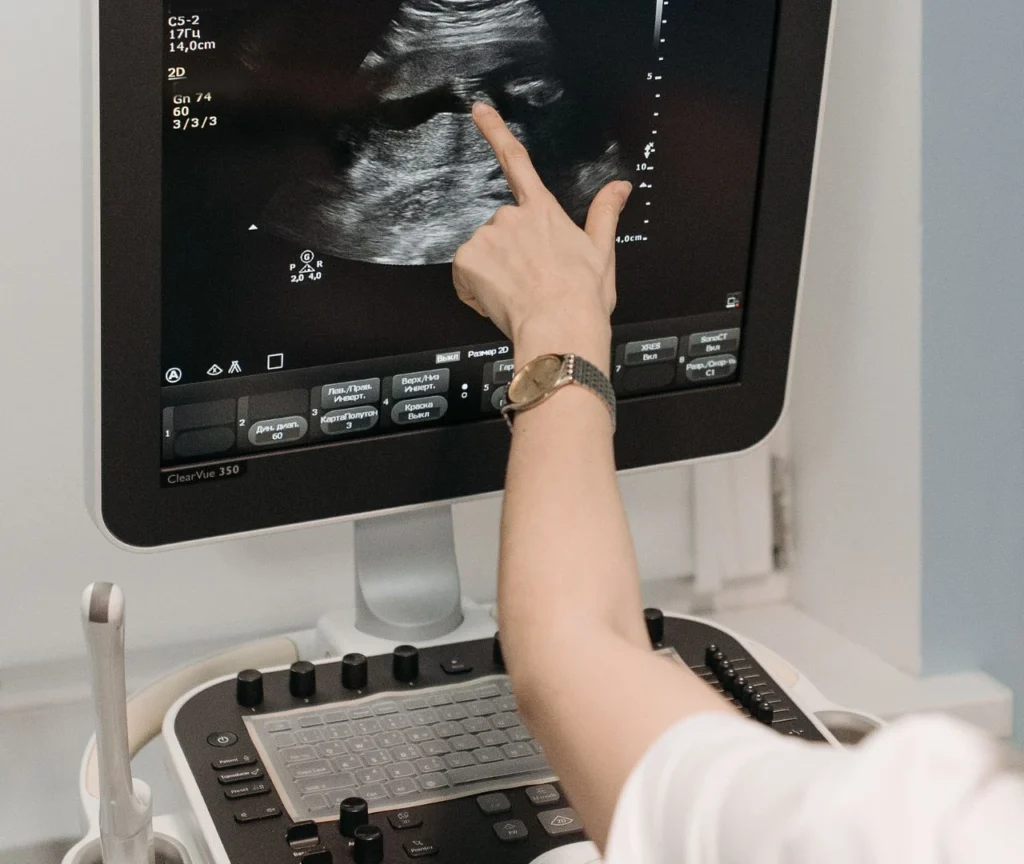

Interacción de los Ultrasonidos con los Tejidos y su Aplicación en Ecografía

Los ultrasonidos interactúan con los tejidos biológicos de manera compleja, y esta interacción depende de diversas propiedades físicas, como la frecuencia de las ondas ultrasónicas, la naturaleza de los tejidos…